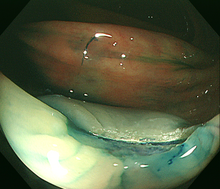

2)内視鏡的粘膜切除術(EMR)

大腸にできた小さな腫瘍やポリープが平坦または陥凹した形の場合、ポリープにスネアが掛かりにくいため、粘膜下に生理食塩水などを注入して隆起させ切除します。切除する病変の大きさや形状によりますが、1日から数日間の入院が必要です。